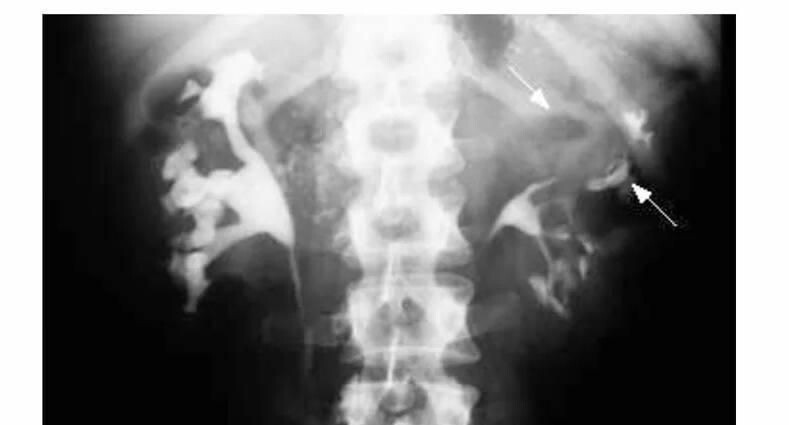

Специалисты провели ультразвуковое исследование и компьютерную томографию органов брюшной полости, а также забрюшинного пространства и обнаружили абсцесс левой почки. Данная патология требовала немедленного корректного лечения.

«В противном случае она может нарушить функции почки и привести к серьезным осложнениям — сепсису, почечной недостаточности и распространению инфекции на другие органы», — пояснила детский уролог-андролог Юлия Аникеева.

«Мы сделали небольшой разрез в поясничной области под ультразвуковым контролем с установкой дренажной трубки в полость абсцесса. После эвакуации гнойного содержимого полость абсцесса была промыта антисептическим раствором. Параллельно проводилась интенсивная антибиотикотерапия», — рассказала Юлия Аникеева.